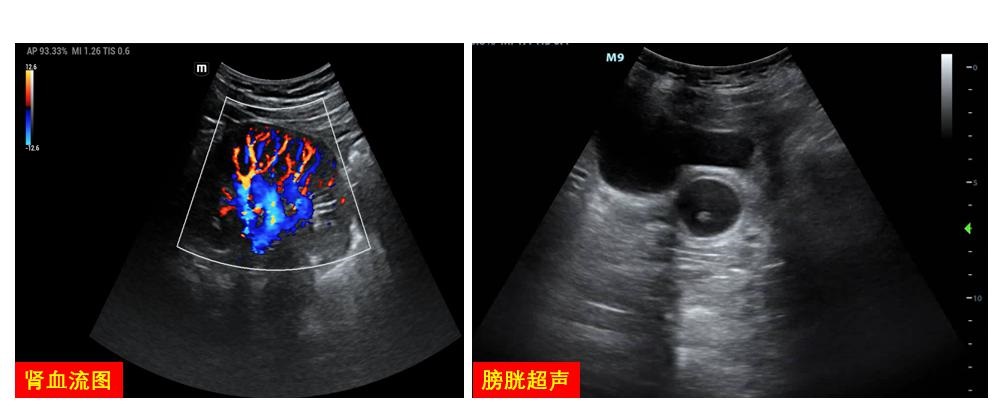

肾脏血流图可协助评估肾灌注情况,调节VA-ECMO流量,并明确发生AKI的原因。在实施过程中,对输尿管、膀胱的探查可快速明确少尿/无尿的肾后性梗阻因素(图 22)。

|

| 图 22 泌尿系统图 |